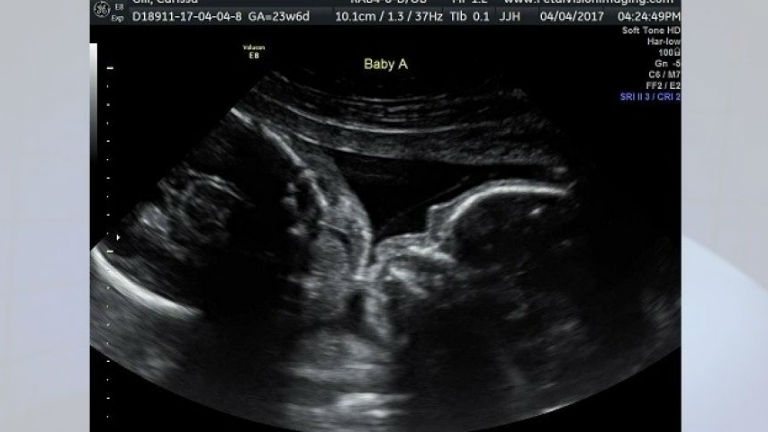

Letarolja az internetet az anyaméhben puszilkodó ikrek fotója